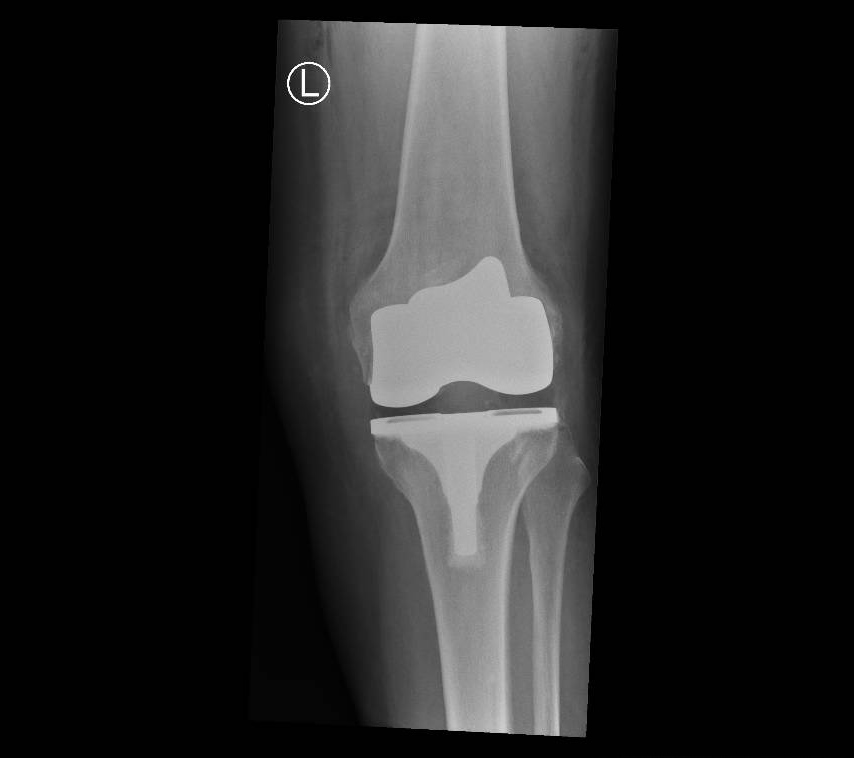

Total Knee Replacement

When more than one compartment (medial, lateral, patella) of the knee wears out and non-operative treatment options have failed a total knee replacement is required.

If the arthritis within the knee affects more than one compartment then a total knee replacement may be recommended.

In a conventional knee replacement, instruments are used to perform the bony cuts and restore the knee back to its original (mechanical) position. This involves releasing some of the ligaments and soft tissues around the knee so that a balanced, full range of motion is achieved at the end of the surgery.

Through a midline incision the surfaces of the bone can be replaced. The femoral component is a smooth metal component of varying sizes, which fits over the end of the femur. The tibial component consists of a metal base plate that sits on top of the tibia and a polyethelene (plastic) insert that fixes onto the tibial component. The patella surface may be replaced if it is worn. The implants are positioned and fixed to the bone using bone cement.